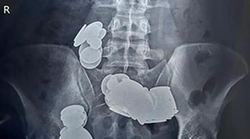

Švicarski skijaš slobodnog stila Jonas Lenherr imao je sreće u nesreći. U ožujku ove godine pri padu je ozlijedio stopalo i za dlaku izbjegao amputaciju. 35-godišnjak je slomio donji lijevi gležanj, zbog čega je morao na operaciju. Sezona je za njega odmah završila.

Slomljena kost je tijekom operacije fiksirana vijcima. Nekoliko tjedana nakon operacije osjećao je jake bolove koje su liječnici pripisivali šarafima. Međutim, ni nakon uklanjanja vijaka ništa se nije promijenilo. "Još uvijek sam imao natečeno stopalo. Bilo je puno krvi. Jako me boljelo. Nisam više mogo opteretiti stopalo navečer. Nikakve tablete protiv bolova nisu pomogle. Nisam znao što se događa, “ rekao je za Blick.